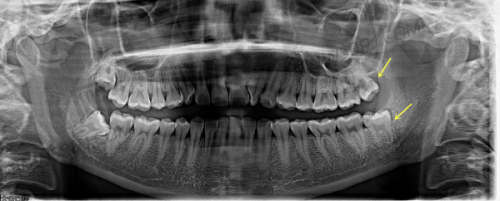

| 全景X光检查 | ¥100~200 | 新客免费 | 含初诊方案定制 |

在医院整体档次这块,德韩口腔属于标准的“中高端口腔机构”,在连锁体系中算非凡学霸级别:用的是德国卡瓦CT,数字化导板种植技术、全景X光、3D扫描这些全配齐,而且医生必须经历层层筛选,临床经验10年以上的才有资格加入主诊。